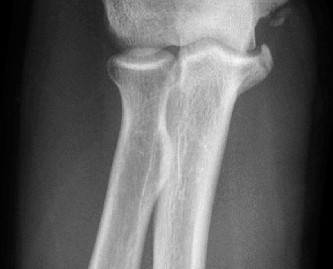

Rotator cuff tears are a common reason for shoulder pain and a common reason to obtain shoulder imaging. As a result, numerous different imaging modalities exist offering different pros and cons. Plain films are still the initial imaging modality of choice. These are most useful in ruling out other possible diagnosis but can help with the diagnosis of a rotator cuff tear as well. Changes to the tendon itself

may appear as calcific tendinosis, which would most commonly be seen at the bone–tendon interface. A decrease in the acromiohumeral distance (less than 2 mm) may also be indicative of a cuff tear. In late cases of rotator cuff tears, superior subluxation of the humerus may be evident. Certain variations in acromial anatomy, including spurs or a hook-shaped (type 3) acromions, may be associated with rotator cuff tears as well. With progression of rotator cuff tears, degenerative changes including spurs, cysts, and sclerosis may be evident at the greater tuberosity. In late, massive tears one may see degenerative changes consistent with rotator cuff arthropathy.